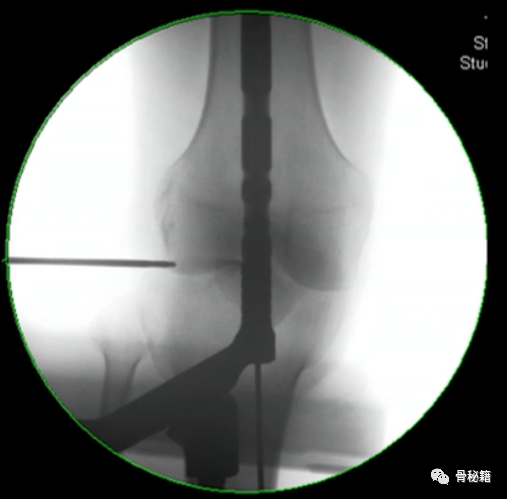

5、钉子的深度。逆行髓内钉的最佳深度是布鲁门萨线的顶点位置,正位居中

近端一般是小粗隆水平以上

6最后提一点锁钉的小技巧,不要造成主任打主钉5分钟,我们锁钉2小时。我们透视的时候,要把锁定空透成两个圆形,但是在操作中往往是椭圆形,这个时候根据椭圆形的长轴来方向来移动C臂,就可以透一个好的圆形了,在此情况下完成锁钉就相对容易些。